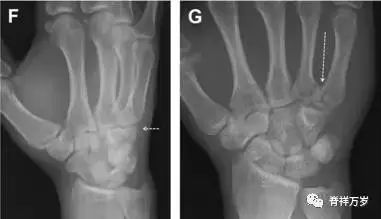

31.舟状骨骨折

舟状骨骨折 60%~70% 发生于腰部,15% 发生于近极, 10% 发生于远极, 8% 发生于远端关节面。除了常规的前后位、侧位、斜位片外,还需要拍专门的舟状骨位片(腕关节尺偏,以舟状骨为中心的腕关节前后位片),特别是鼻烟壶有压痛时。

图 2 舟状骨骨折 (A、B)第 1 例患者,舟状骨远极关节内骨折(白色箭头),斜位片显示较清楚(B);(C、D)第 2 例患者,舟状骨腰部骨折(虚线箭头),斜位片显示较清楚(D);(E~H)第 3 例患者,舟状骨近极骨折,常规 X 线片均未看到骨折,而在舟状骨位片上才能见到骨折(虚线圆)。